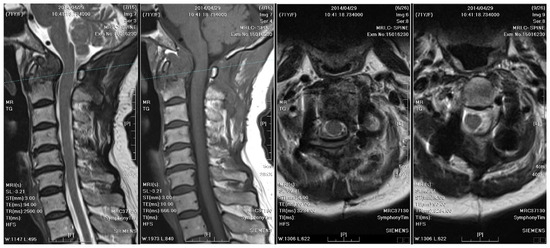

Two years after surgery, the patient experienced progressive weakness in the left upper limb and numbness in both upper limbs, which dramatically worsened within a week. A follow-up cervical spine MRI with contrast showed right rotatory C1–C2 subluxation with bony destruction and surrounding soft tissue enhancement at the atlanto-odontoid joint, leading to severe spinal cord compression with focal myelomalacia (Figure 5). The atlantoaxial abscess progressed and led to myelopathy.

Distinctive MRI characteristics help differentiate between tuberculous and pyogenic spondylitis. Tuberculous abscesses typically exhibit a thin and smooth wall, while thick, irregular, and ill-defined walls are associated with pyogenic infections [16]. TB often results in heterogeneous contrast patterns of vertebral body enhancement and bony destruction exceeding 50%, compared to pyogenic infections. On the other hand, the fragmentary or osteolytic pattern of bone lesions on CT images was a predictor for spinal TB, with an odds ratio of 3.3 [17]. Furthermore, the combination of the above CT finding and three MRI features (thin abscess wall, destruction of more than half of the vertebral body, and subligamentous spread) had an even higher diagnostic value (odds ratio of 15.58) [17]. The first cervical spine MRI and CT of our case revealed severe bony destruction (but less than 50%), heterogeneous contrast enhancement of the vertebral body, and subligamentous spread in the prevertebral area. The wall of the abscess was ill-defined, smooth, and regular. However, the thickness of the wall was equivocal (Figure 2). A cervical spine MRI performed due to progressive weakness two years later revealed a thinner abscess wall, as well as a heterogeneously enhanced vertebral body and subligamentous spread (Figure 5). From the above, although the literature has generalized several radiological traits for diagnosing spinal TB, imaging findings can still be inconclusive.

Figure 5. MRI of the cervical spine checked two years after the initial surgery demonstrates right rotatory atlantoaxial subluxation with bony destruction and surrounding soft tissue enhancement at the atlanto-odontoid joint, leading to severe spinal cord compression with focal myelomalacia. A thinner abscess wall (compared to the cervical spine MRI from two years ago), heterogeneously enhanced vertebral body, and subligamentous spread were observed.